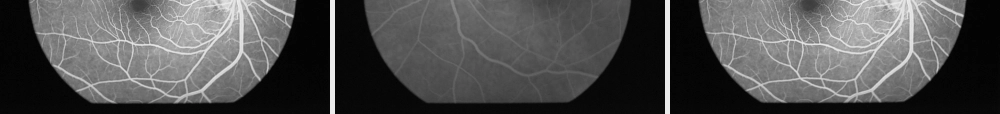

眼底血管荧光造影诊断技术:眼底病诊断重要技术脉络膜视网膜视神经提供依据:治疗选择、疗效观察、预后、发病机制与检眼镜眼底检查比较•动态观察•毛细血管水平•血管功能•脉络膜循环及色素上皮改变•激发光紫蓝光(465~490nm)荧光素钠荧光黄绿光(520~530nm)•原理眼底血供•睫状后短动脉•视网膜中央动脉视盘血供•睫状后短动脉分支•视网膜中央动脉毛细血管血视网膜屏障1:视网膜血管内皮细胞2:视网膜色素上皮正常情况荧光素钠不能通过该屏障疾病归类•循环动态异常•视网膜屏障功能损害•视网膜血管结构异常•色素上皮损害•脉络膜损害•视乳头损害循环动态异常•充盈迟缓•充盈缺损•动静脉吻合•逆行充盈视网膜屏障功能损害1:内屏障损害血管荧光渗漏血管壁损害毛细血管扩张新生血管2:外屏障损害荧光渗漏于网膜下中浆、原田氏病等视网膜血管结构异常•毛细血管扩张•毛细血管闭塞•侧支管道与动静脉短路•新生血管•动脉瘤与血管瘤色素上皮损害•屏障功能损害•萎缩•色素上皮脱离•玻璃膜疣•色素上皮异生与增殖脉络膜损害•脉络膜充盈迟缓•脉络膜毛细血管闭塞•脉络膜新生血管视乳头损害•荧光增强•荧光减弱造影及造影前准备•散瞳•过敏史、肝肾功,血压•荧光素钠:一种大分子染料,毒性小,不参与代谢。造影前过敏试验。•3秒内静推完染料,极少数人有恶心、呕吐。正常血管造影分期•动脉前期•动脉期•动、静脉期•静脉期•晚期动脉前期动脉期动、静脉期静脉期晚期正常黄斑荧光异常眼底荧光•低荧光:遮蔽荧光、充盈缺损•高荧光:透见荧光、异常血管、渗漏、积存、着色•原田氏病脉络膜毛细血管闭塞低背景荧光BRVO造影荧光表现黄斑出血遮蔽荧光AMD遮蔽荧光充盈缺损•BRVO血管闭塞区形成•视网膜中央动脉阻塞动脉充盈缺损透见荧光黄斑色素上皮损害透见荧光萎缩性改变)异常血管•BRVO新生血管•糖网新生血管•糖网新生血管膜•中渗新生血管•视网膜毛细血管扩张症(Coats病)中浆渗漏、积存、着色新生血管渗漏及血管壁渗漏•原田氏病荧光渗漏、积存•原田氏病荧光渗漏、积存先天黄斑缺损•葡萄膜炎黄斑囊样水肿•黄斑部视网膜前出血•视盘水肿•视盘有髓神经纤维